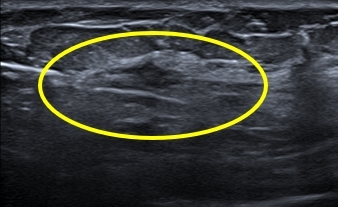

충분한 국소마취를 통하여 합병증 없이 총조직검사를 안전하게 시행하는 과정입니다.